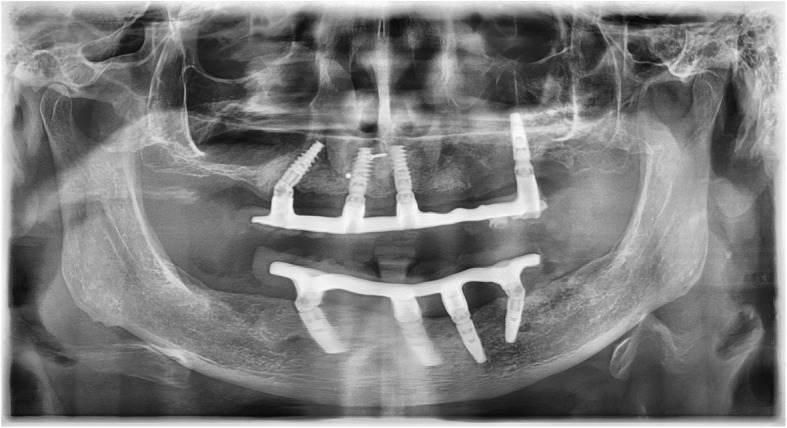

Fig. 2.

The procedure of what was done in case of an implant loss. The X-ray shows an All-on-4 restoration on four implants. The angled implant in the 2nd quadrant was loosened. For this reason, another implant with an external sinus elevation was placed in this area. During the entire healing period of this implant, the All-on-4 restoration was fixed on the remaining four implants, so that there was no load on the newly inserted implant

This X-ray records the integration of the redesigned restoration of the case in Figs. 2 and 3. The loosened implant was explanted